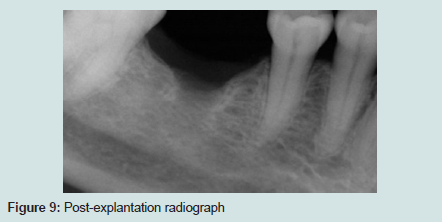

The patient was examined again four months post explantation and another CBCT was taken. A significant diminishing of the parethesia had occurred, described by the patient as a 40% improvement. The patient felt tingling on both sides of her face, and could not differentiate clearly the area of the numbness. In addition, a consistent sign of socket healing was noted on CBCT (Figures 8b and 9).